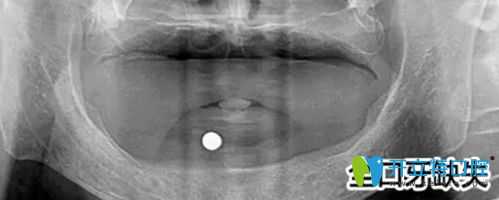

郭先生的口腔全景片:

鎮(zhèn)江拜博口腔為郭先生拍攝的口腔全景圖

之后萬院長給郭先生做了詳細的檢查,首先給郭先生做了口腔全景片的檢查,發(fā)現(xiàn)郭先生前牙骨量不足,壁薄,需要植骨才能進行種植牙手術(shù)。

種植需要避開手術(shù)后的骨缺失區(qū),所以對種植體的承受力和穩(wěn)定性要求較高,同時郭先生對美觀要求較高。萬院長根據(jù)郭先生的需求與口腔情況后為他進行了植骨手術(shù),傷口愈合后,萬院長為他進行CT掃描后確認可以進行種植牙手術(shù)。